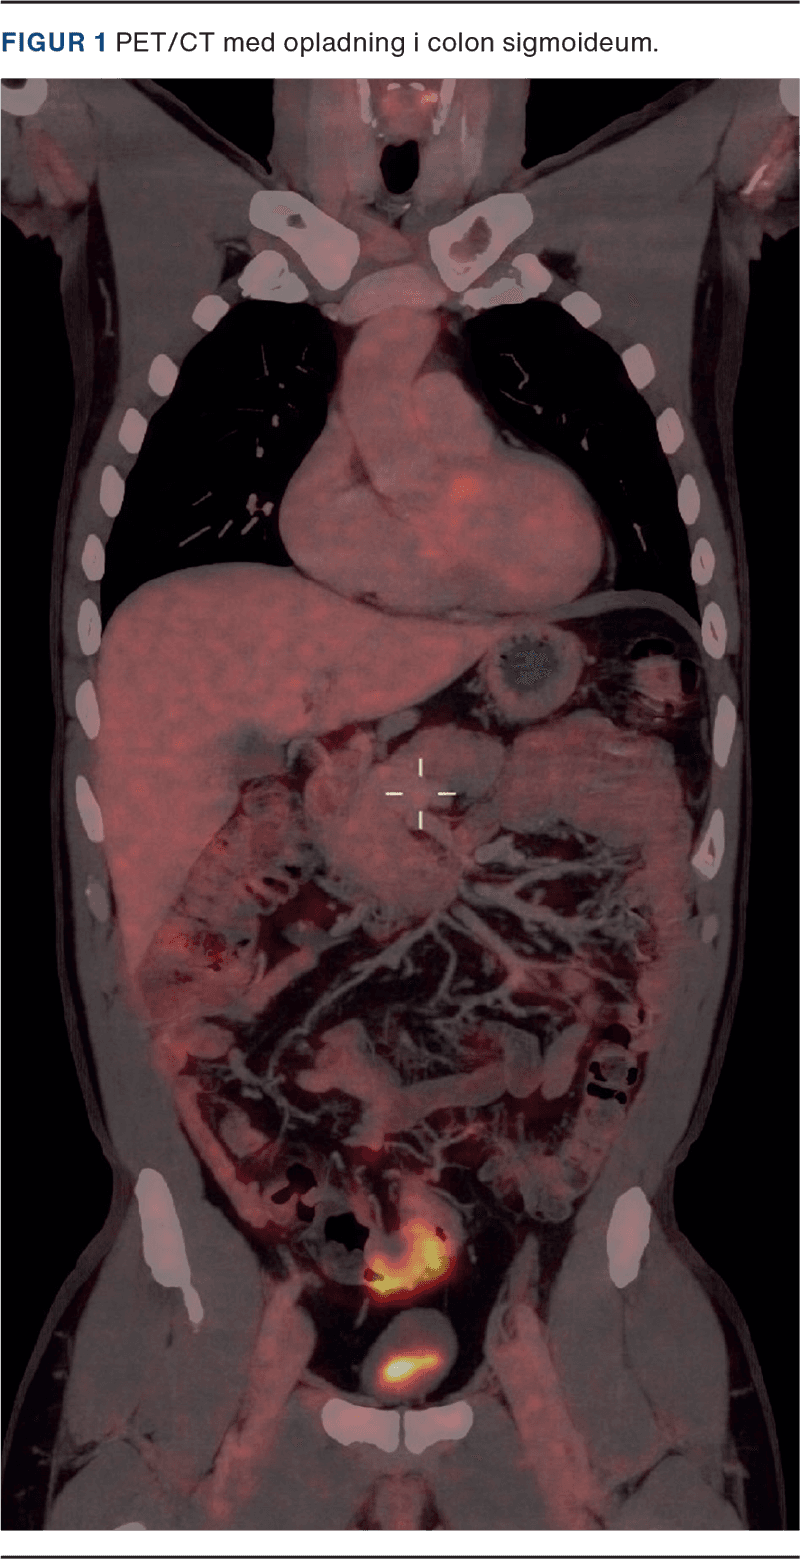

En 54-årig mand, tidligere kendt med højresidig hydrocele, opsøgte egen læge med smerter og hævelse svarende til højre testis. Patienten havde ingen gastrointestinale gener eller B-symptomer. På mistanke om epididymitis henvistes patienten til UL-undersøgelse, hvor der sås en solid tumor i højre scrotum tæt ved caput epididymis. Der blev primært mistænkt et leiomyosarkom, og patienten blev henvist til urinvejskirurgisk afdeling i pakkeforløb. Yderligere UL viste, at tumoren var afgrænset fra testis, men trykkede på denne. Mistanken blev rettet mod en adenomatoid tumor. Med usikkerhed omkring tumorens oprindelse, negative tumormarkører laktatdehydrogenase (LDH), alfaføtoprotein (AFP) og humant choiongonadotropin (HCG), og da CT ikke egnes til at klassificere uklare skrotale forandringer, blev patienten booket til operation. Der udførtes højresidig ingvinal eksploration med frysemikroskopi, hvor der blev fjernet en 1-2 cm stor tumor nær caput epididymis, og der opstod mistanke om mesoteliom, hvorfor der blev gennemført semikastratio. Histologi viste metastase af adenokarcinom, formentlig fra colon. En PET/CT (Figur 1) viste vægfortykkelse i colon sigmoideum, og patienten henvistes til koloskopi og efterfølgende robotassisteret laparoskopisk sigmoideumresektion. Histologi viste adenokarcinom med gennemvækst af peritoneum og metastaser til seks ud af 30 lymfeknuder, klassificeret som T4N2M1-adenokarcinom. Patienten påbegyndte adjuverende kemoterapi med capecitabin og oxaliplatin (CaPox). Ved seneste kontrol den 18.09.2024 var patienten rask uden tegn på recidiv.